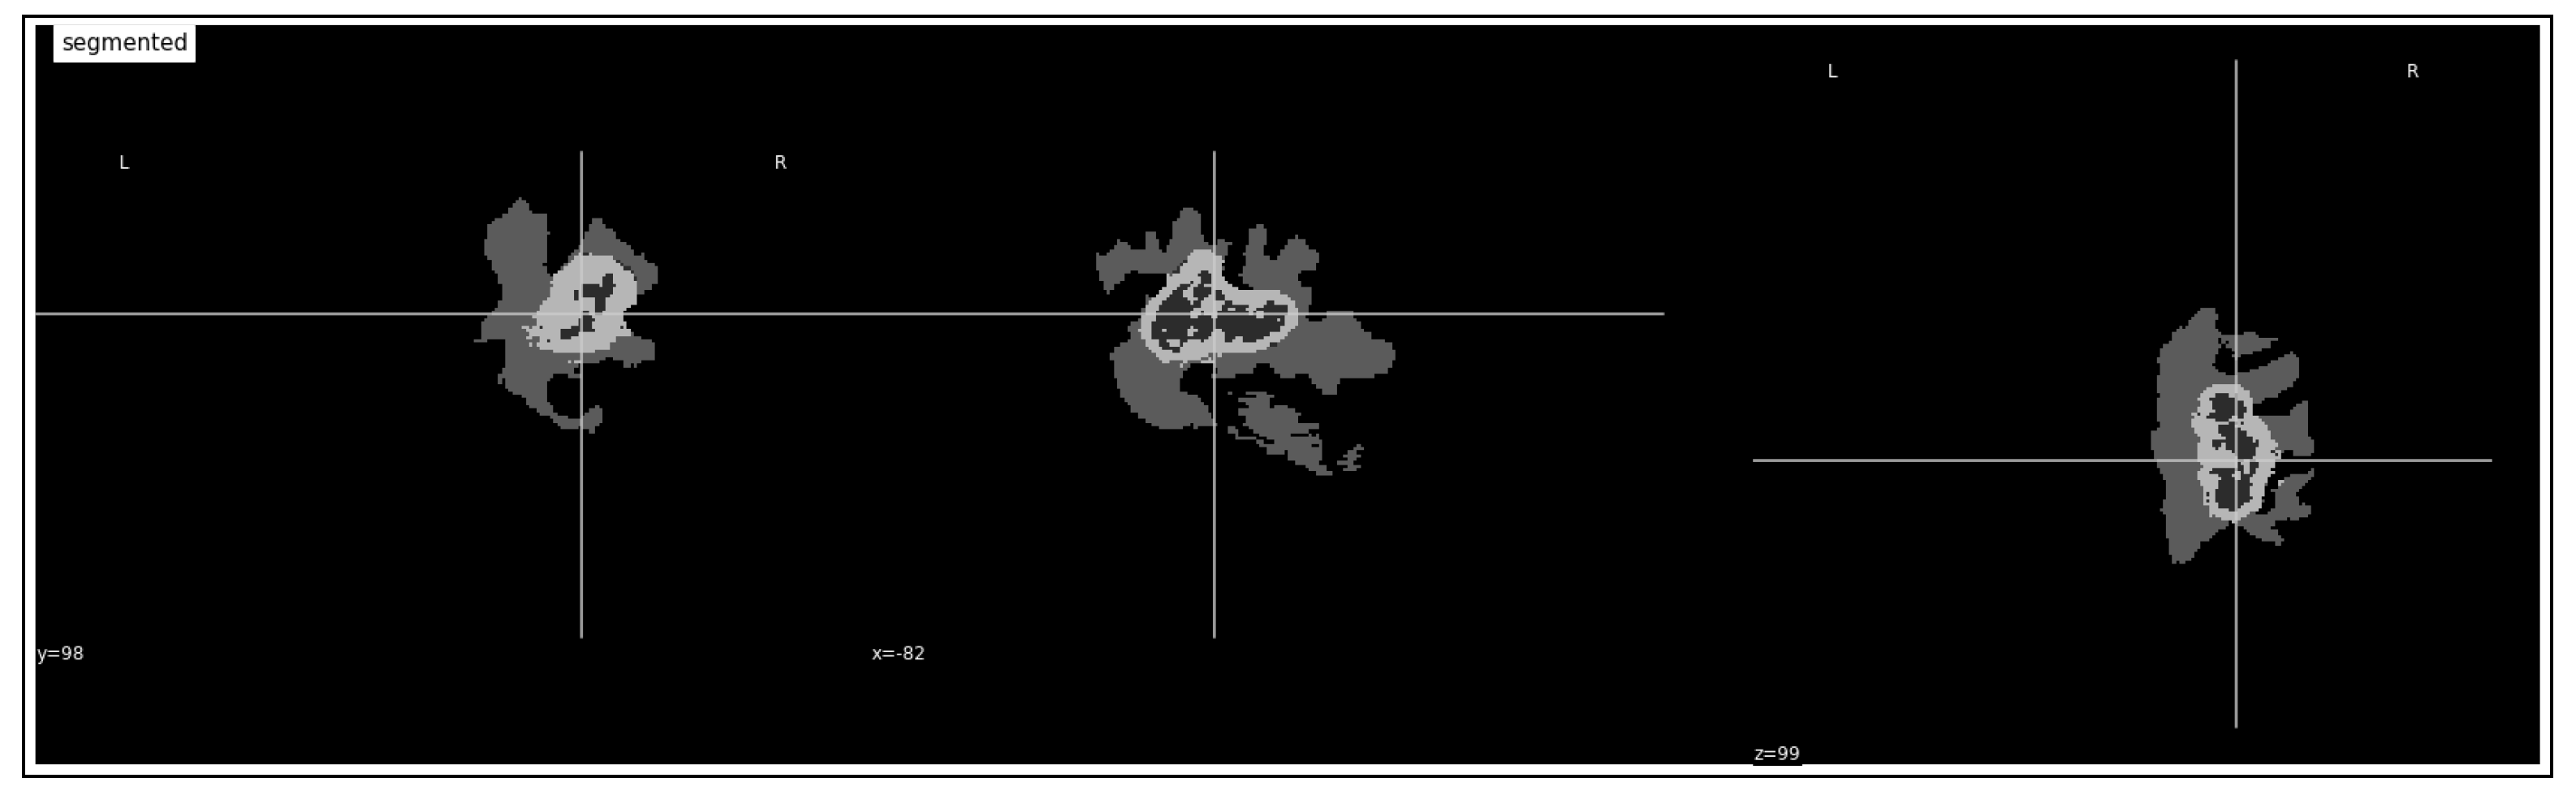

3.2. Tumor Identification

3.3. Tumor Volume Computation

4.3.1. Tumor Identification

| Dice Coef | Accuracy | Precision | Sensitivity | Specificity |

|---|---|---|---|---|

| 0.25 | 0.96 | 0.95 | 0.90 | 0.99 |